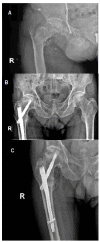

Avascular necrosis (AVN) of the femoral head is caused by disruption of the blood supply to the proximal femur. The alterations in the blood supply may occur following a traumatic event or result from a non-traumatic cause. Femoral neck fracture and hip dislocation and associated surgical procedures, corticosteroid therapy, and alcohol abuse frequently lead to AVN development. Type of fracture (displaced or undisplaced) and time between injury and surgery are the most critical factors in assessing the risk of developing AVN. Diagnosis of AVN can be established based on patients' complaints, medical history, and radiographic findings. There is no consensus on the treatment of patients with AVN to date. Non-surgical methods are dedicated to patients in the early pre-collapse stages of the disease and consist of pharmacotherapy and physiotherapy. Surgery is recommended for patients with advanced disease.